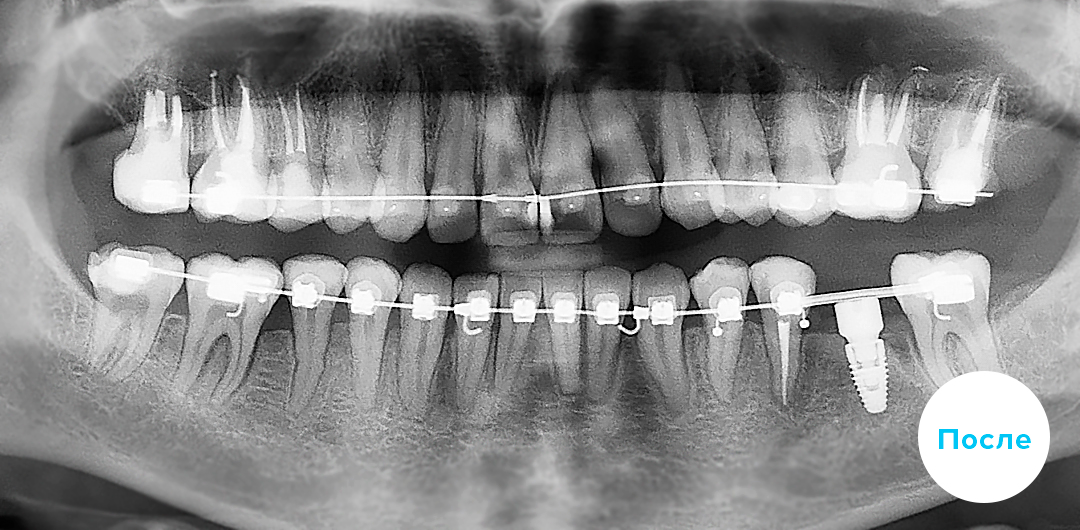

До

После

ИМПЛАНТАЦИЯ 3 ЗУБОВ С ПРЕДВАРИТЕЛЬНОЙ ОРТОДОНТИЧЕСКОЙ ПОДГОТОВКОЙ

Смотреть кейс